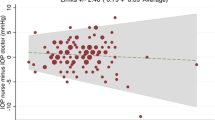

Correlation of noninvasive tonometry in mice with OHT

We further sought to directly evaluate the correlation between IOPG and IOPR in vivo in a setting that mimics laboratory conditions using a population of mice with a range of IOPs. In order to induce different degrees of IOP, we induced OHT in a cohort of animals (n=46) by diode laser cauterization of the trabecular meshwork. Using the methods described above, laser cauterization resulted in moderate elevation of IOP in operated eyes 1 day after laser treatment when compared to control eyes (P=7.18 × 10−10 in Goldmann tonometer and P=3.57 × 10−15 in rebound tonometer, paired t-test), and IOP elevation in the laser-treated eye persisted throughout the 2-week observation period (Figure 4a and b, P<0.001 in both tonometers). The preoperative mean IOP (±SD) of all eyes was 16.3±1.5 mmHg by Goldmann tonometry and 11.3±2.0 mmHg when determined by rebound tonometry (P=8.03 × 10−27). This difference in tonometer readings of approximately 5 mmHg was also evident at each subsequent examination time point. The correlation between IOPG and IOPR was moderate (r=0.70) (Figure 4c) and the limit of agreement was large (mean difference 4.8 mmHg, 95% limit of agreement −0.6–10.3 mmHg). However, the overall IOP increase following laser treatment and the subsequent slow decline of IOP was clearly evident regardless of the measurement method. When the average per cent increase in IOP of laser-treated vs control eyes was analysed, both methods yielded more similar data (Day 0, P=0.92; Day 1, P=0.01; Day 3, P=0.80; Day 7, P=0.99, and Day 14, P=0.25) (Figure 4d).

IOP changes in mouse eyes measured by (a) Goldmann and (b) rebound tonometry after laser treatment. Laser cauterization resulted in moderate elevation of IOP in operated eyes 1 day after laser treatment when compared to control eyes, and IOP elevation in the laser-treated eye persisted throughout the 2-week observation period (P<0.001 in both tonometers). (c) Data obtained are moderately correlated and suggest that IOP measured by Goldmann are typically higher than those by rebound (The line of equality is depicted as a dotted line). (d) Relative increase of IOP as determined by the two methods.